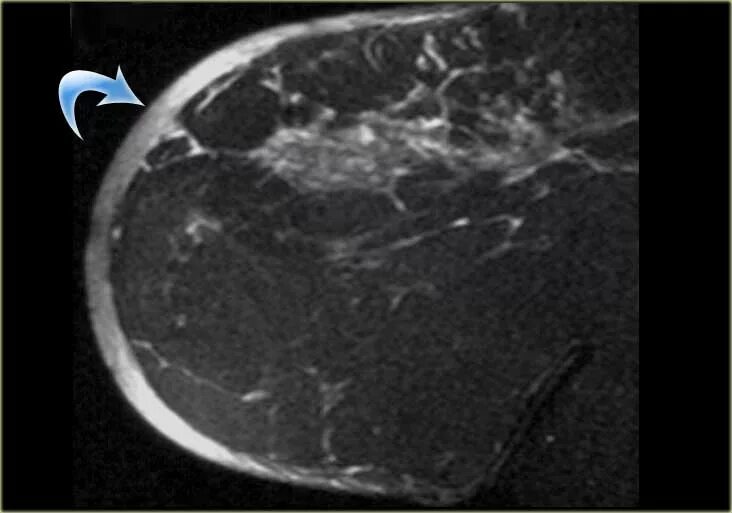

Отечная форма рака молочной